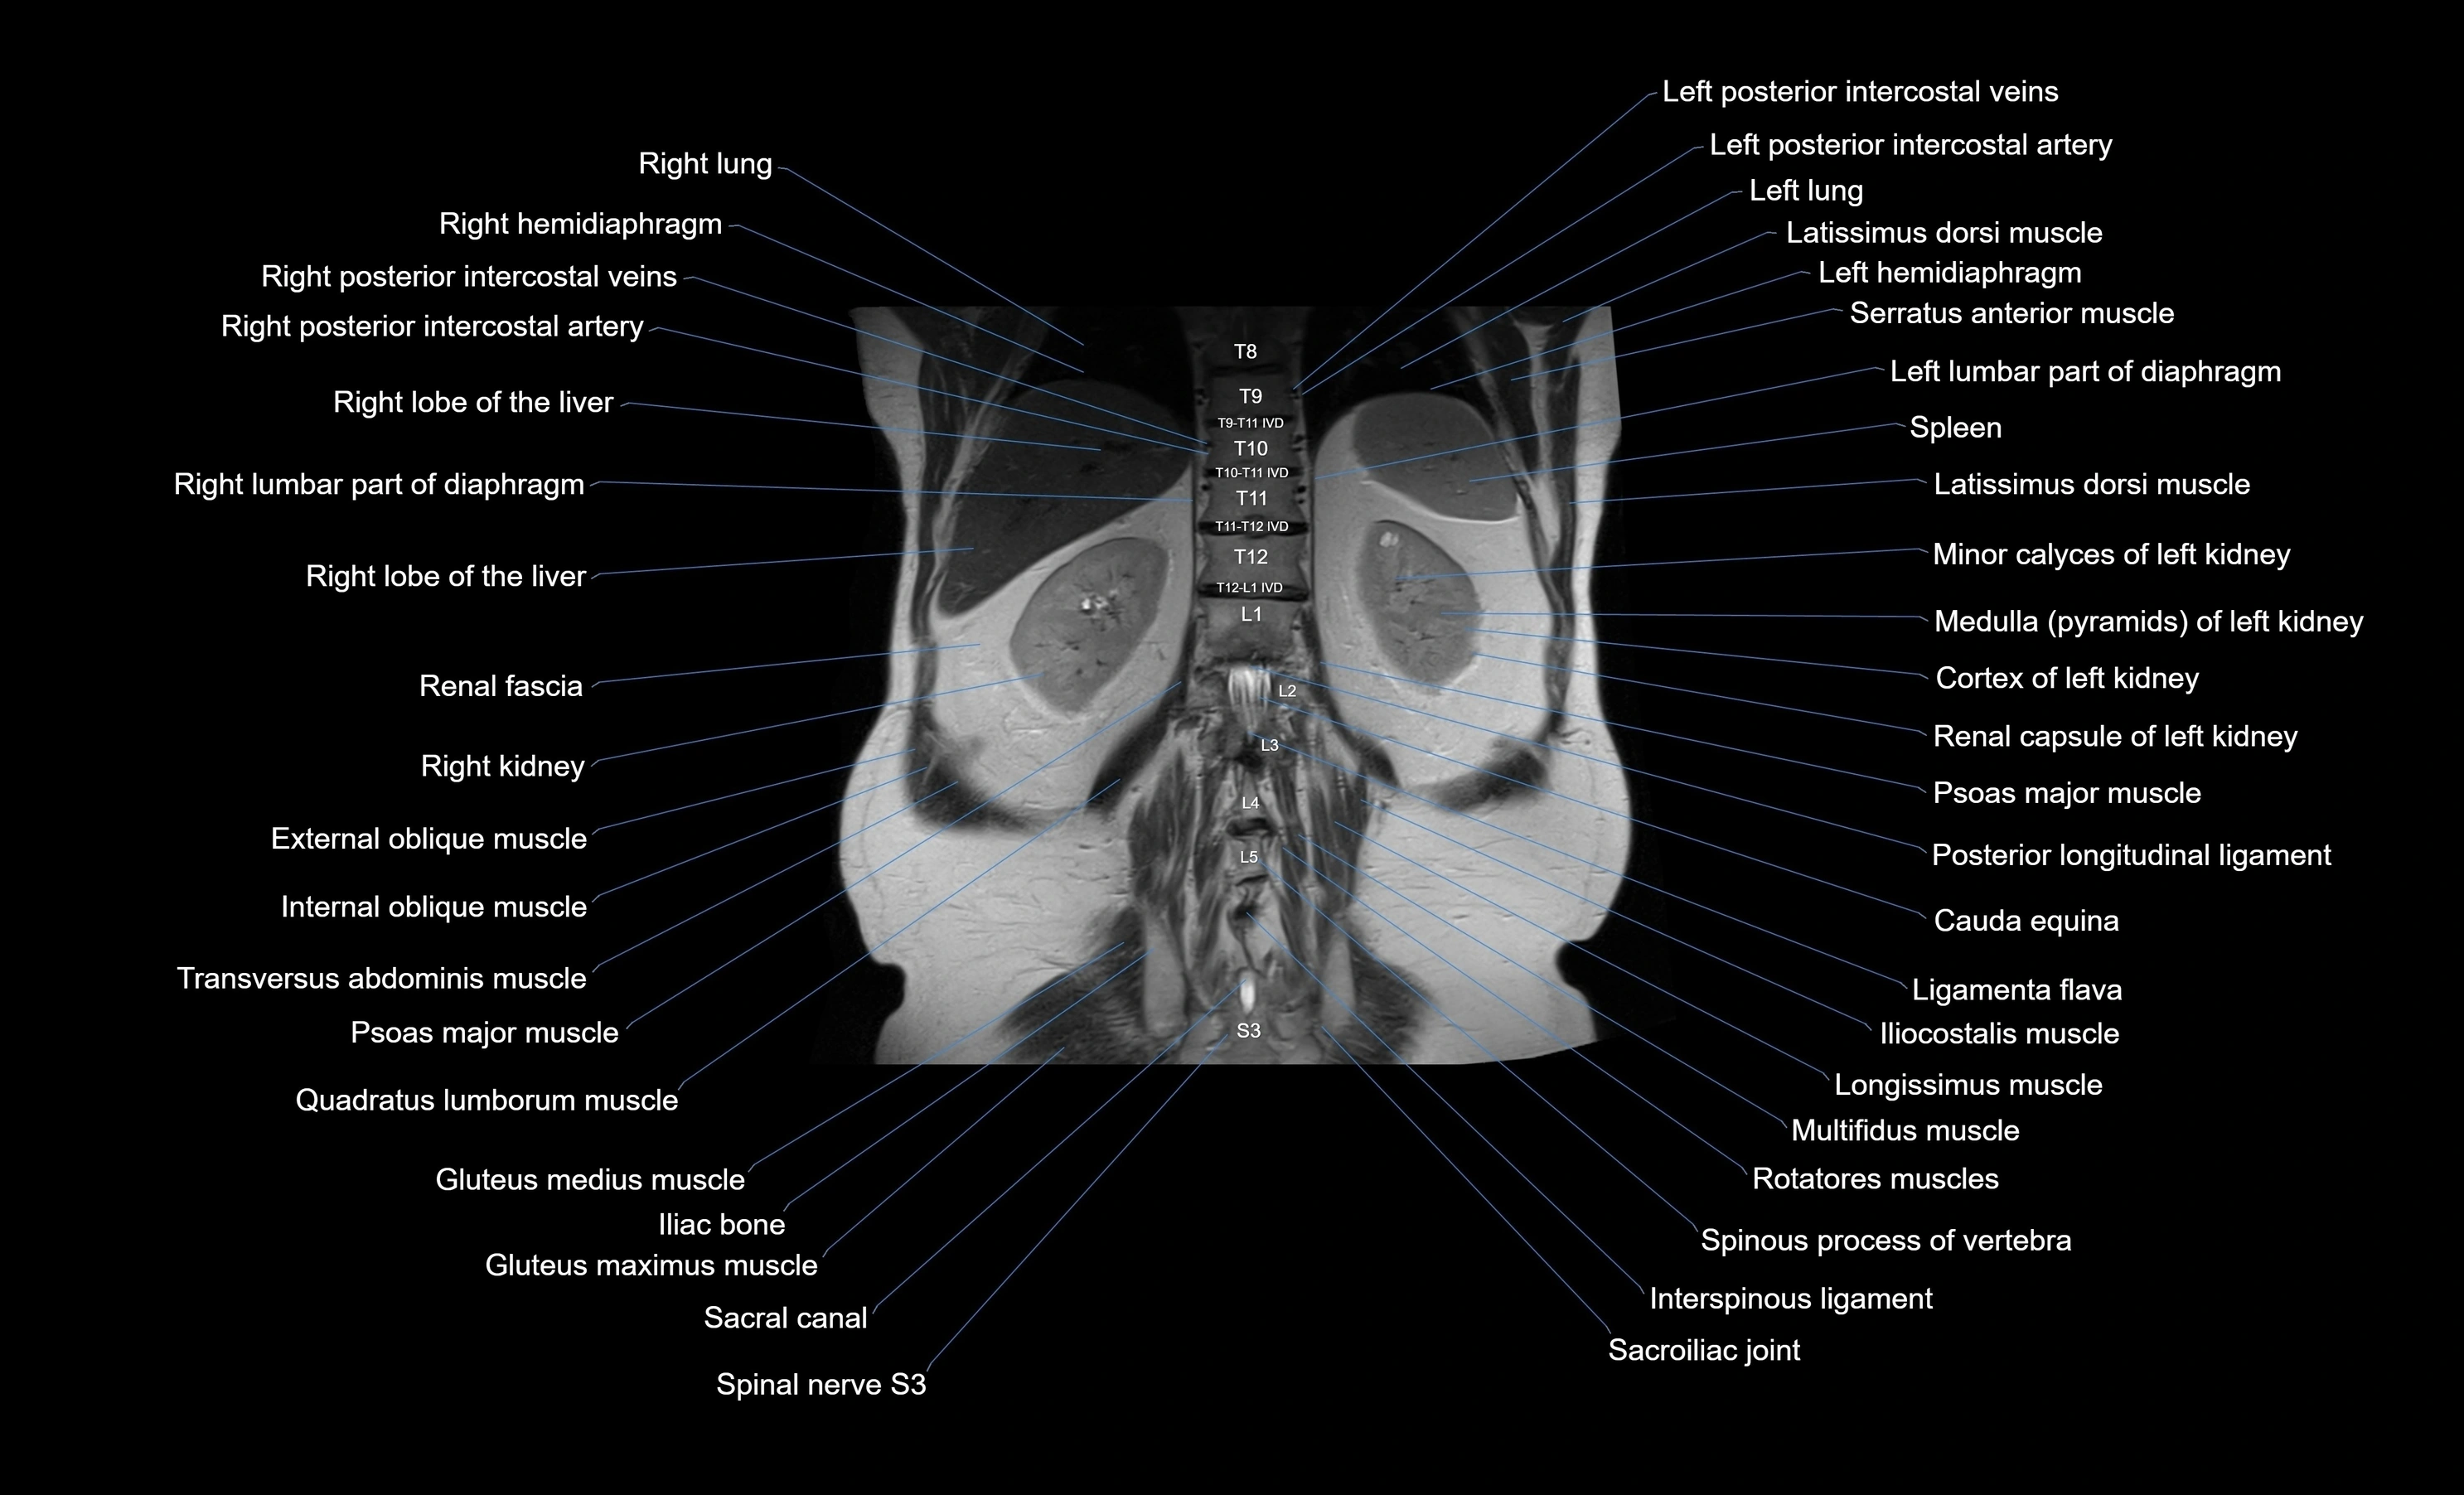

- Cauda equina

- Latissimus dorsi muscle

- Left hemidiaphragm

- Left kidney

- Psoas major muscle

- Quadratus lumborum muscle

- Gluteus maximus muscle

- Gluteus medius muscle

- Posterior longitudinal ligament

- Ligamenta flava (Ligamentum flavum)

- Sacral canal

- Spinal nerve S3

- Spleen